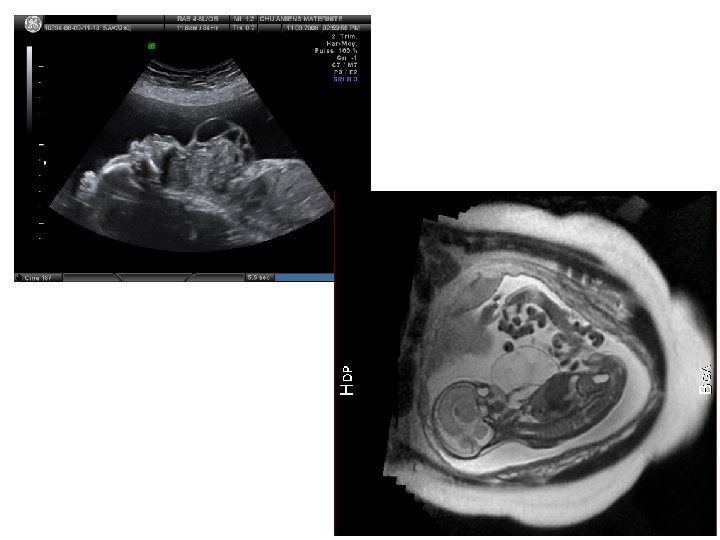

IRM foetale • Pas en 1ère intention • Indiquée à partir de la constatation d’une anomalie fœtale à l’échographie anténatale • IRM cérébrale fœtale +++ • IRM pour pathologie fœtale en dehors du système nerveux : – Thorax – Bilan de masse (bilan anatomique précis)